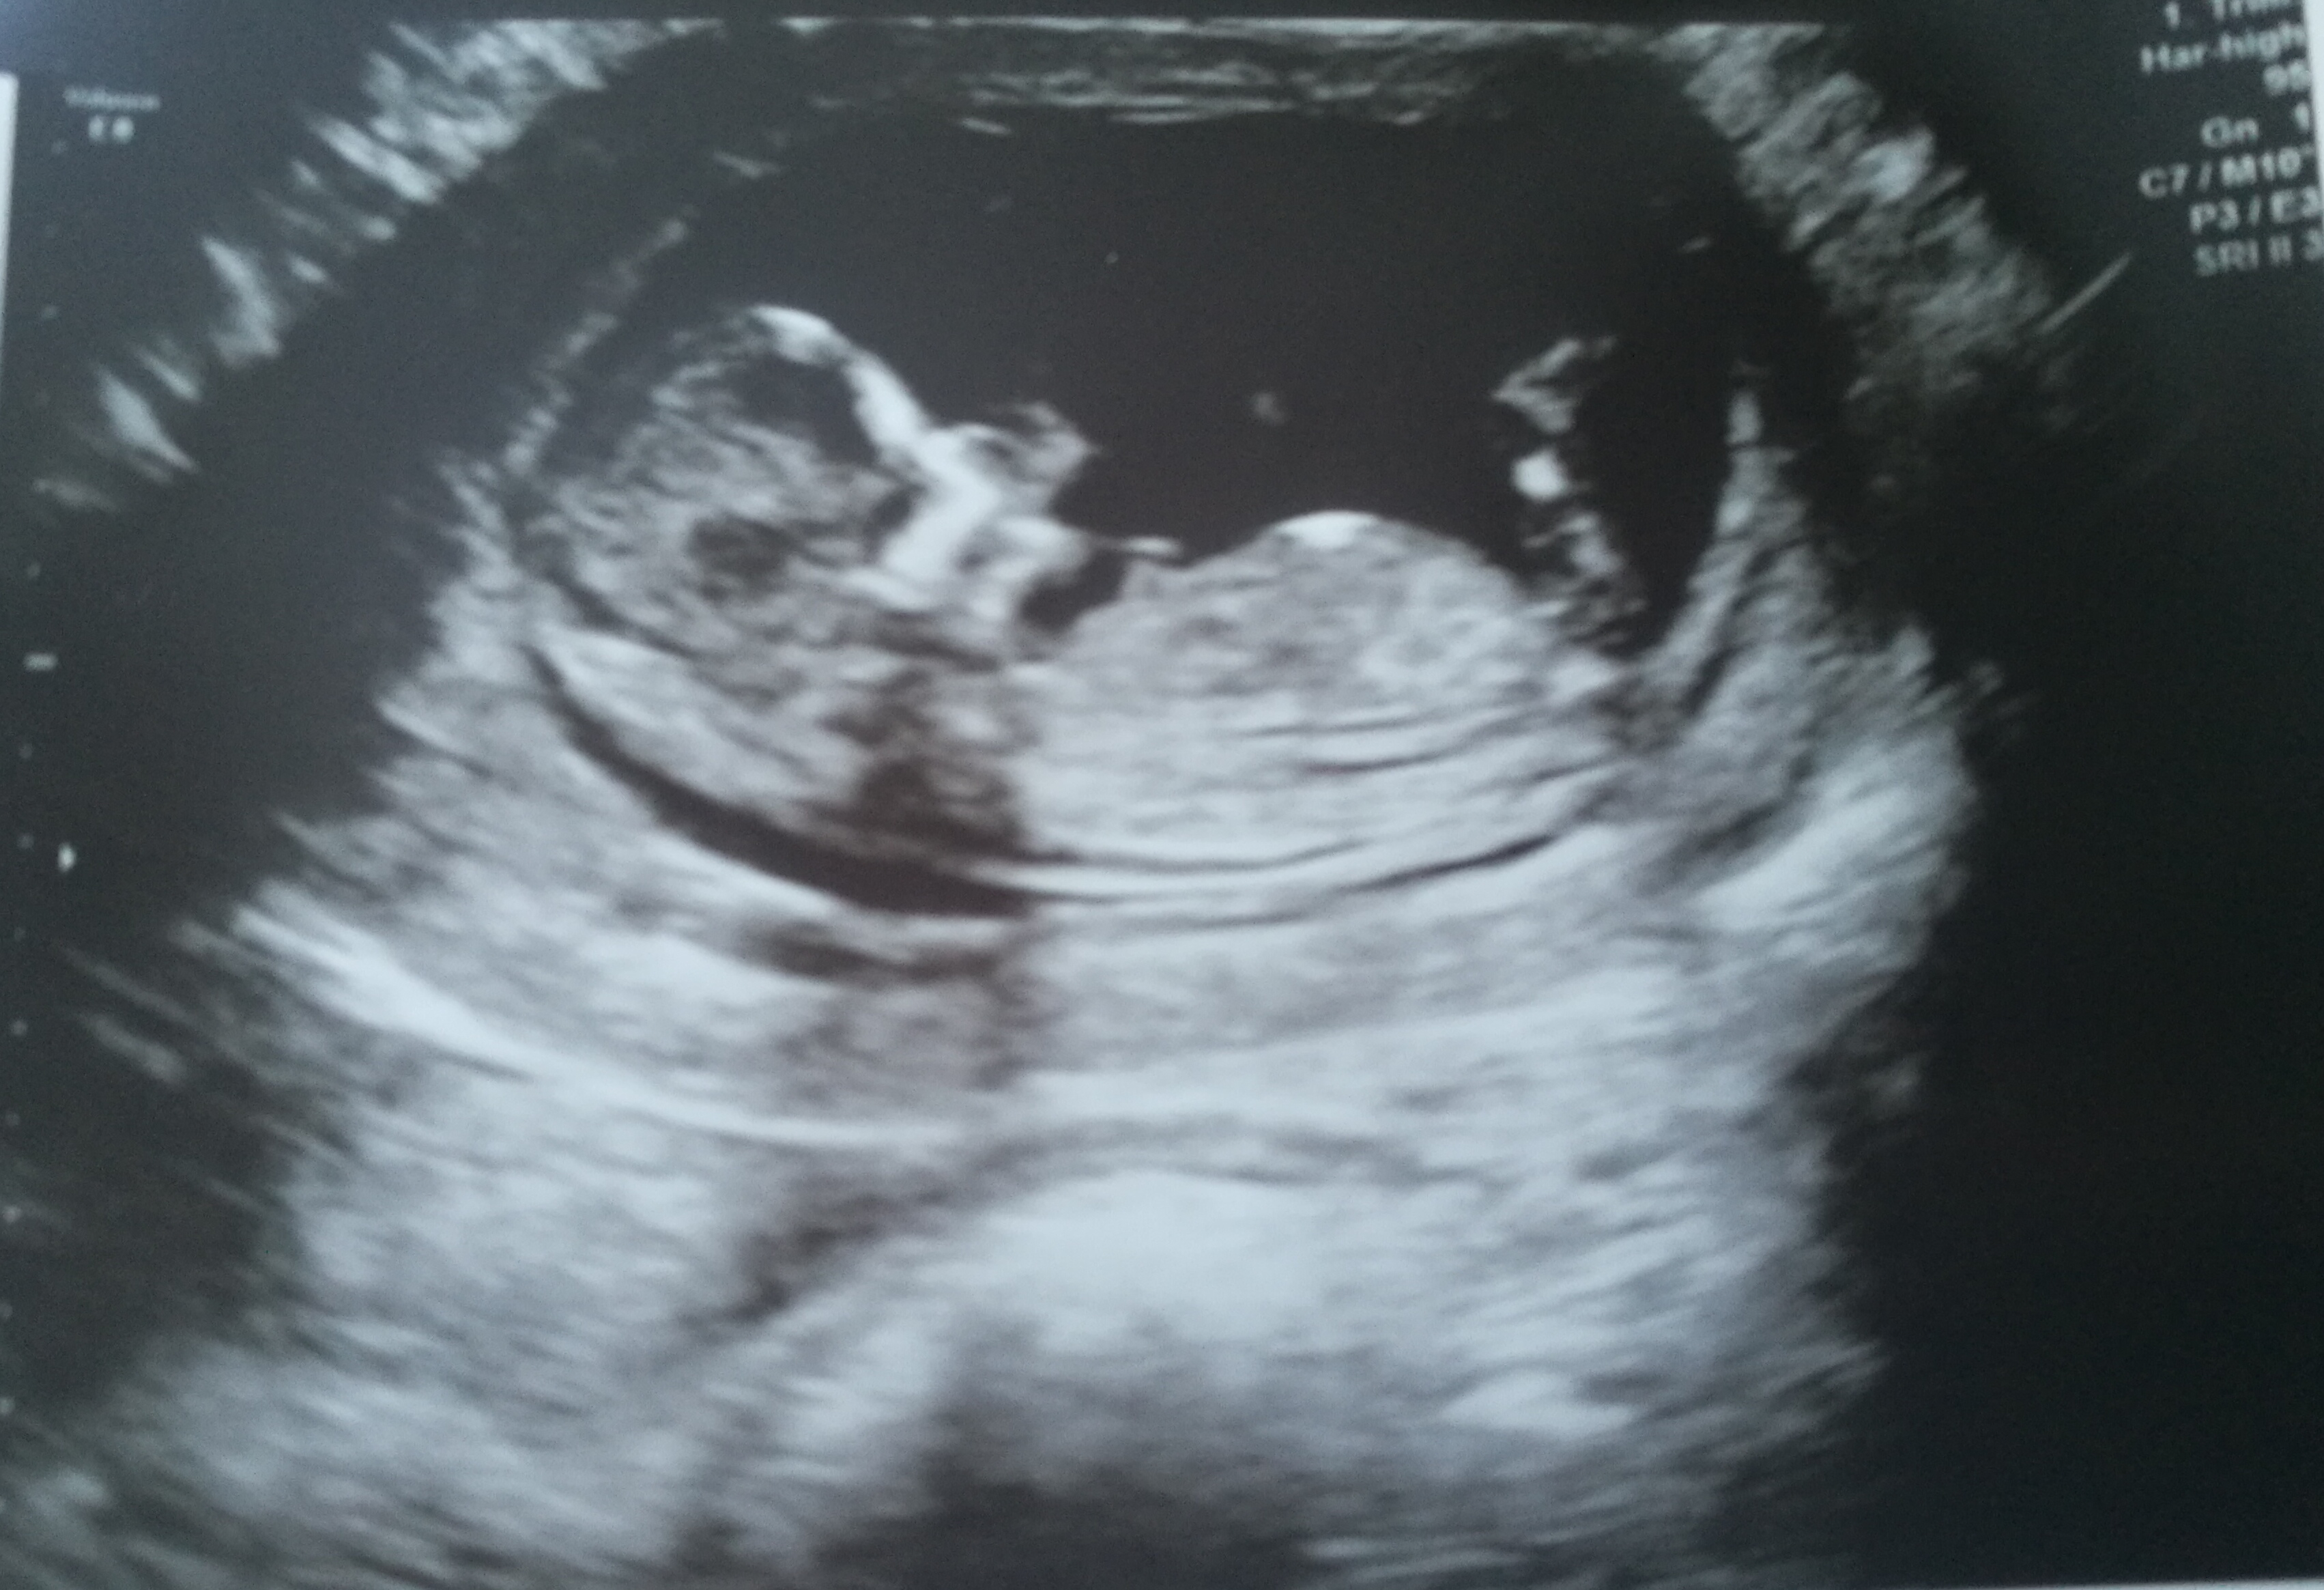

Hi everyone can you please help wht do you think its girl or boy nub this scan is 12weeks pregnant.

I don't see a nub, sorry. 12 weeks is a bit early anyway as the nub may rise.

The nub looks flat so...girl?